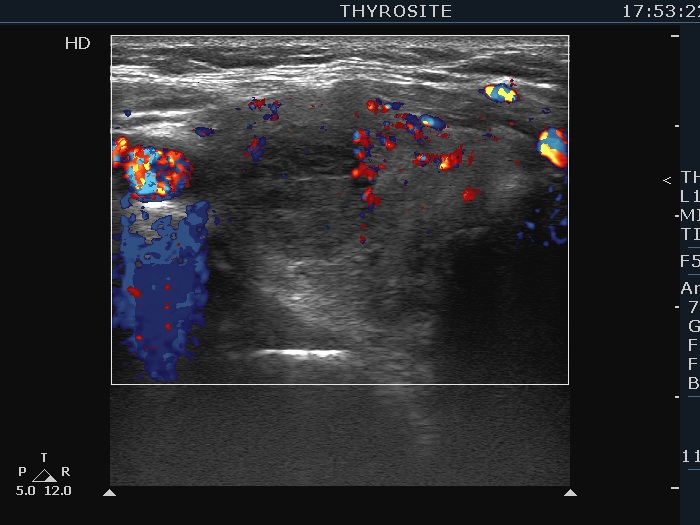

Three years after the first examination (third row of images):

Clinical presentation. The patient has ceased the thyrostatic therapy for six months. Recently, she noticed again complaints suggesting hyperthyroidism.

Palpation: unchanged.

Results of blood tests: hyperthyroidism (TSH undetectable, FT4 39.1 pM/L).

Ultrasonography. There were two changes compared with the previous examination. The thyroid has become echonormal while the lesion in the right lobe has become again hypoechoic.Suggestion: daily 20 mg methimazole. Radioiodine therapy when the FT4 level will become normal.